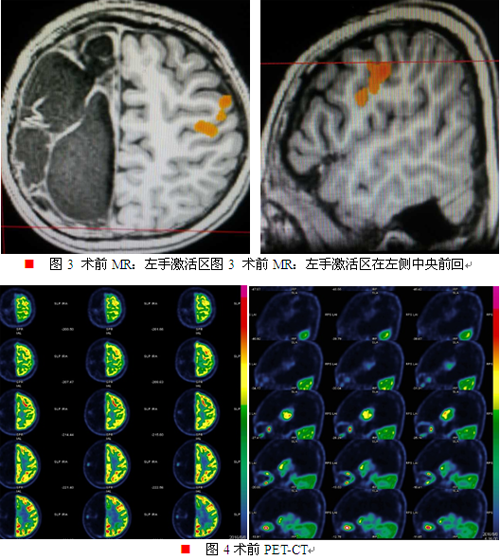

辅助检查:MR薄层扫描检查提示:1.右侧大脑半球及左侧额叶多发软化灶形成,并胶质增生、囊性脑萎缩;2.胼胝体发育不良;3.右侧内囊后肢、丘脑及大脑脚异常改变,考虑沃勒变性(如图一所示)。视频脑电图:异常脑电图III,间歇期:1.右半球半球生理节律减弱;2.癫痫样放电,①弥漫性,②右半球。发作期:BATS→过度运动,脑电图提示中线区著。fMRI:活动左侧肢体,右侧半球中央区未见激活,左侧半球SMA、中央前后回可见激活(如图二、三所示)。PET:右侧半球残存组织低代谢,左侧颞极及颞叶内侧结构低代谢(如图四所示)。IQ/MQ:全量表46,言语55,操作41,韦氏记忆<51。视野检查不配合。wada试验提示左侧为语言优势半球,左侧肢体运动功能已代偿转移到左侧大脑半球。